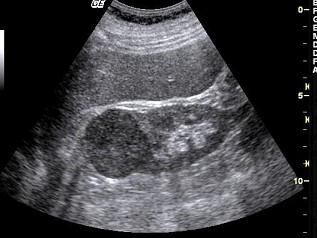

男性,45岁,因出现无痛性血尿半月余就诊,根据超声声像图提示,最可能的诊断是?(?)A.肾细胞癌B.肾结核C.肾囊肿D.肾脓肿E.肾结石

问题 男性,45岁,因出现无痛性血尿半月余就诊,根据超声声像图提示,最可能的诊断是?(?)

选项 A.肾细胞癌 B.肾结核 C.肾囊肿 D.肾脓肿 E.肾结石

答案 A